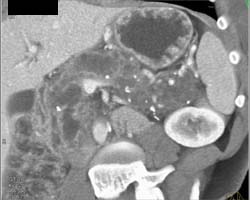

Dilated Common Bile Duct (CBD) With Ampullary Tumor